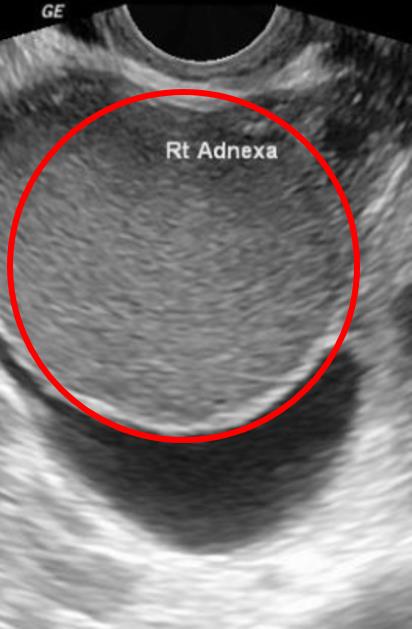

A 31-year-old woman presents to her gynecologist with a 3-month history of right-sided pelvic pain. She first noticed the symptoms during sexual intercourse with a new partner. Since then, she has noticed similar pain with defecation. She was treated for chlamydia with appropriate antibiotics 3 months ago. Her menstrual cycles are regular, occurring every 28 days with 5 days of moderate bleeding, and her last period was 10 days ago. She is nulliparous, has no other medical history, and takes no medications. The patient does not use tobacco, alcohol, or illicit drugs. Her temperature is 99.5°F (37.7°C), blood pressure is 110/60 mmHg, pulse is 80/min, and respirations are 16/min. Examination reveals a small, retroverted uterus with cervical motion tenderness. Transvaginal ultrasound reveals the mass shown in Figure A on the right ovary. Which of the following is the most likely cause of this patient's symptoms?

This patient with dyspareunia, chronic pelvic pain, and dyschezia, most likely has endometriosis. The presence of a mass on the ovary is consistent with an endometrioma.

Figure/Illustration A is an ultrasound of the ovary demonstrating a homogenous mass (red circle). This appearance is consistent with a diagnosis of an endometrioma.

Answer 4: Mature teratoma can cause pelvic pain, but ultrasound findings typically reveal calcified, heterogenous nodules. This patient has a homogenous nodule on her ovary that is more consistent with an endometrioma.